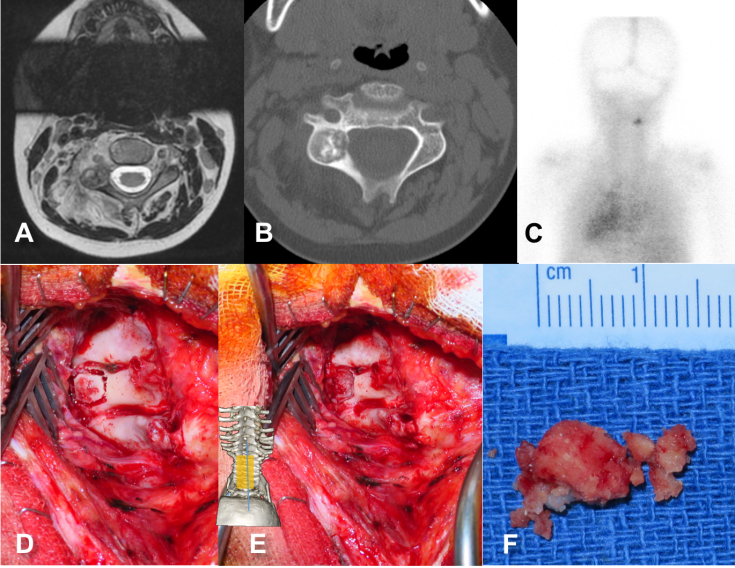

le torticolis symptomatique d’une tumeur médullaire

s’accompagnant souvent de douleurs nocturnes

l’imagerie montre une inclinaison plutôt qu’une rotation

le torticolis symptomatique d’une lésion rachidienne

par exemple un ostéome ostéoïde (Cf. ci-dessous), qui peut provoquer des douleurs chroniques, nocturnes et échapper longtemps aux investigations.